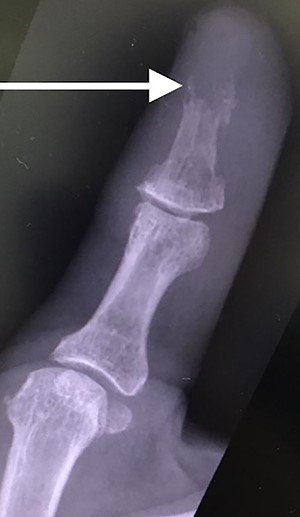

Her blood tests on presentation were unremarkable and X-rays of her right thumb showed a lytic lesion involving the tuft of the distal phalanx (Figs. 4 and 5). She was admitted to the hospital and was treated as having an infection of her right thumb with elevation and intravenous antibiotics. She underwent emergency surgery the next day for a washout and debridement of the right thumb. During the debridement in theatre, there was no pus in the pulp, but the bone was found to be eroded and soft, thus multiple specimens from the bone were sent for microscopy, culture and sensitivity, acid-fast bacilli (AFB) and histopathology.

Lateral X-ray of right thumb showing erosion of tip of distal phalanx and soft tissue swelling.